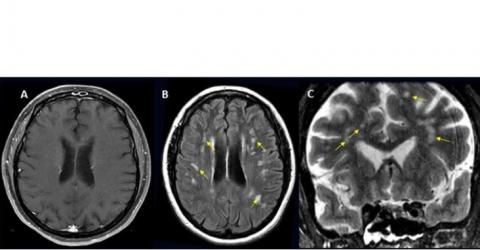

Imagerie du cerveau d'une patiente COVID-19 ayant développé des maux de tête, une forte fièvre puis une ptose de la paupière supérieure droite (Visuel Radiological Society of North America et Scott H. Faro, M.D.)

1,2 % des patients hospitalisés avec le COVID développeront une complication cérébrale

• chez les patients hospitalisés ayant besoin de subir une IRM ou une tomodensitométrie (CT-scan) du cerveau, l'examen s’avère positif (diagnostic d’un problème cérébral) environ 10 % du temps ;

• les complications les plus fréquentes comprennent l'accident vasculaire cérébral ischémique (AIT), avec une incidence de 6,2 %, suivi par l'hémorragie intracrânienne (3,72 %) et l'encéphalite (inflammation du cerveau) (0,47 %) ;

• certaines complications cérébrales rares sont également identifiées telles que l'encéphalomyélite aiguë disséminée (ADEM), une inflammation du cerveau et de la moelle épinière et le syndrome d'encéphalopathie postérieure réversible (SEPR), un syndrome qui induit de nombreux symptômes similaires à ceux de l’AVC ;